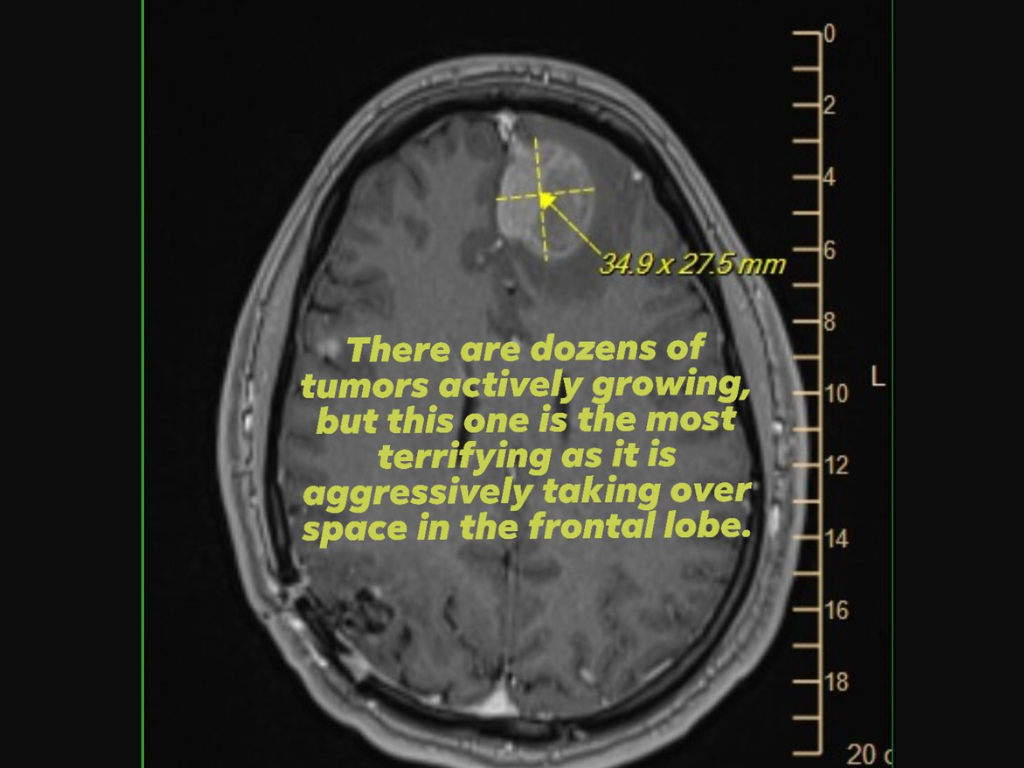

Als bewijs voegde ze ook een afbeelding bij van een hersenscan (MRI) waarop een agressieve tumor van de frontale kwab te zien was, terwijl ze pleitte voor steun of hulp van leidinggevenden bij Epic Games, die de belangrijkste beslissingen namen met betrekking tot de ontslagen.